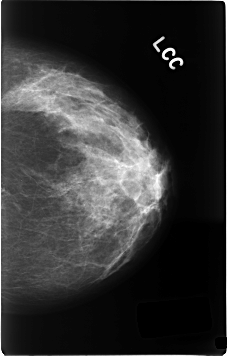

C_0339_1.LEFT_CC

LEFT_CC LINES 4616 PIXELS_PER_LINE 2952 BITS_PER_PIXEL 12 RESOLUTION 50 NON_OVERLAY